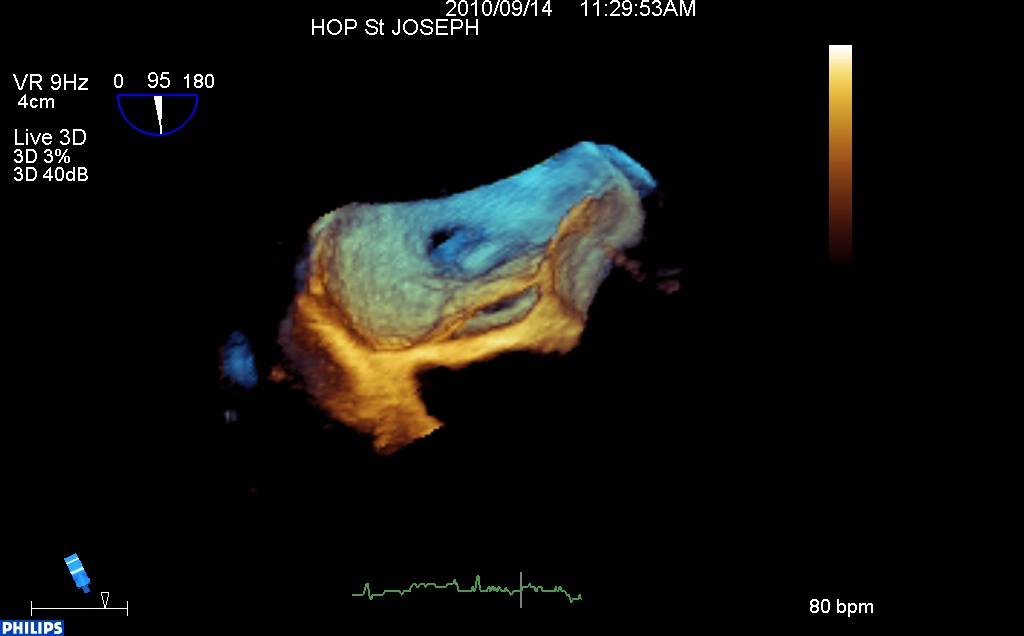

Sur cette image, une fosse ovale sans FOP, mais avec de multiples petites CIA :

Et sur cette image 3D la même fosse ovale devant, en haut et au gauche par une vue intra Oreillette Gauche, avec l’oreillette droite derrière et la veine cave supérieure en haut, en arrière et à droite. Derrière la fosse ovale, un petit trou correspondant à la petite CIA.